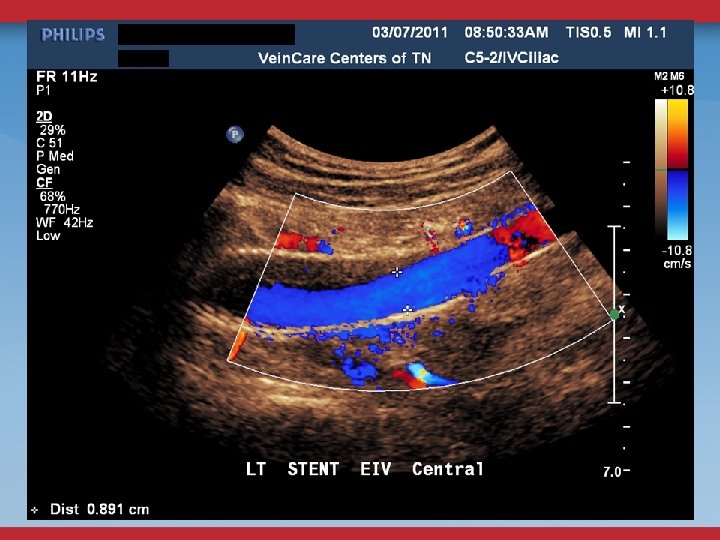

FOLLOW-UP <1 WEEK 3 -4 WEEKS US/OV 3, 6, 9, 12 MONTHS AND ANNUALLY US/OV OFFICE VISIT ABD/PELVIC

1

SECONDARY PROCEDURES FLOW-LIMITING IN-STENT SENOSIS PTBA NEW STENOSIS OUTSIDE STENT PTBA/STENT THROMBOSIS CONSIDER LYSIS EVALUATE INFLOW AND OUTFLOW AND ADEQUACY OF ANTICOAGULATION